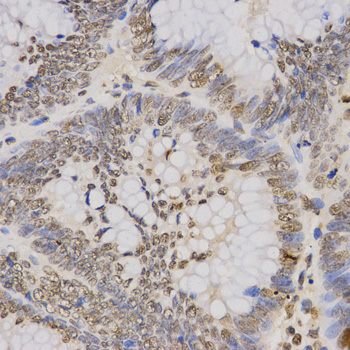

Immunohistochemistry of paraffin-embedded human rectal cancer tissue using H3K79me3 antibody at dilution of 1:200 (x400 lens).